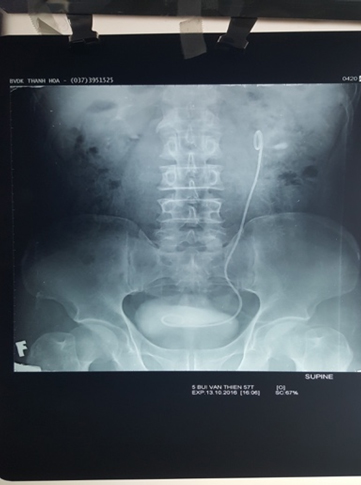

Hình ảnh X-quang đặt sonde JJ trước mổ 2 tuần.